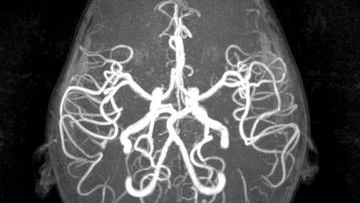

Лучшие методы обследования сосудов головного мозга Для получения точных результатов о качестве кровоснабжения структур головы в медицине используются разные методы обследования сосудов головного мозга. Классификация способов диагностики сосудистой системы мозга основывается: Как называется обследование сосудов головного мозга Любой метод обследования сосудов головного мозга принято называть ангиографией, где “ангио” в переводе с греческого означает “сосуд”, “графия” - “писать”. Она показывает функциональное состояние сосудов, окольного кровотока и протяжённость патологического процесса...